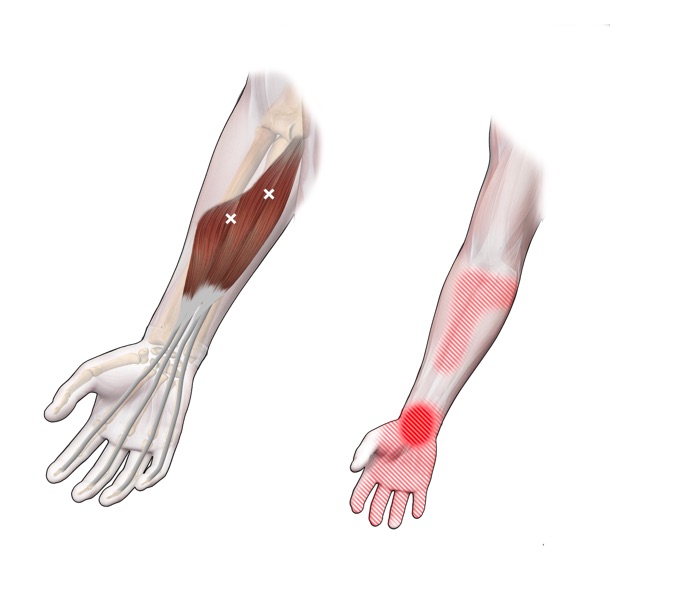

Spieren (Nederlands)

Spieren (nederlands)

Spieren (Latijn)

Spieren (latijn)